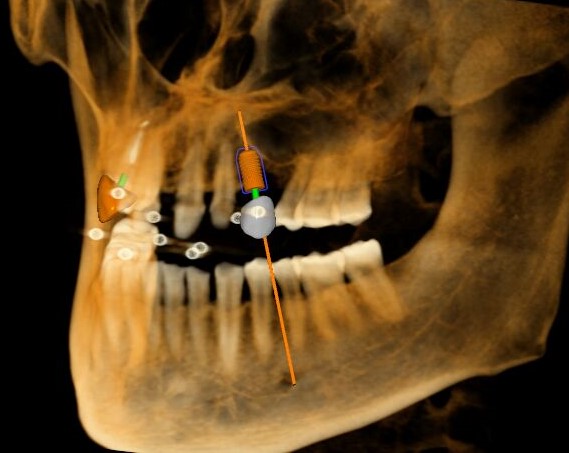

三維視圖

根據(jù)患者CT顯示,使用種植導(dǎo)航軟件設(shè)術(shù)前手術(shù)方案??紤]到患者拒絕手術(shù)摘除上頜竇囊腫等因素,此次手術(shù)選用了Straumann骨水平4.10*8.0mm的植體,植體末端位點(diǎn)設(shè)計(jì)距上頜竇底壁2mm處的同時(shí)兼顧種植方向和修復(fù)間隙,來(lái)達(dá)到理想的效果。

導(dǎo)航下精細(xì)分配修復(fù)間隙,精細(xì)規(guī)劃植入方向,避開(kāi)上頜竇底,精確植入